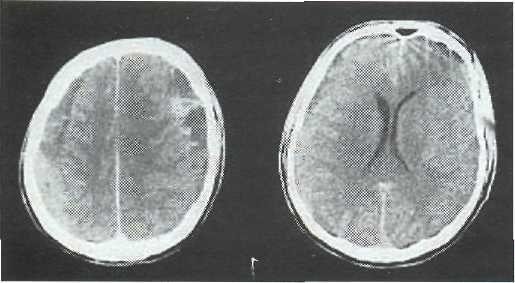

Медицинские аспекты и диагностика субдуральной гигромы мозга